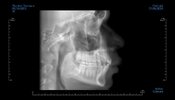

You don’t look like you have an overbite to my in these scansThis is from a CBCT scan

It is… humans are supposed to have slight overbite, like 3-4mm of overlap with front incisors over bottom incisors. His teeth look decent too… I can’t tell if the photo of his skull was not oriented properly or if he has a cant?i agree, or it's at most a very slight overbite

realistically speaking, your bite is pretty good so getting such heavy treatment could easily make your skeletal imbalance look worse + the reason why your midface appears "sunken" is because your infras are recessed, your zygo projection is good thoThe CBCT I sent where from a orthodontic agency but their sales representative just wanted to money grift me and hook in on a almost5k invaslign plan which wouldn’t help with skeletal expansion

The one thing is looking at the frontal view of his x-ray, it appears his facial midline may be off, but I can’t say for surerealistically speaking, your bite is pretty good so getting such heavy treatment could easily make your skeletal imbalance look worse + the reason why your midface appears "sunken" is because your infras are recessed, your zygo projection is good tho